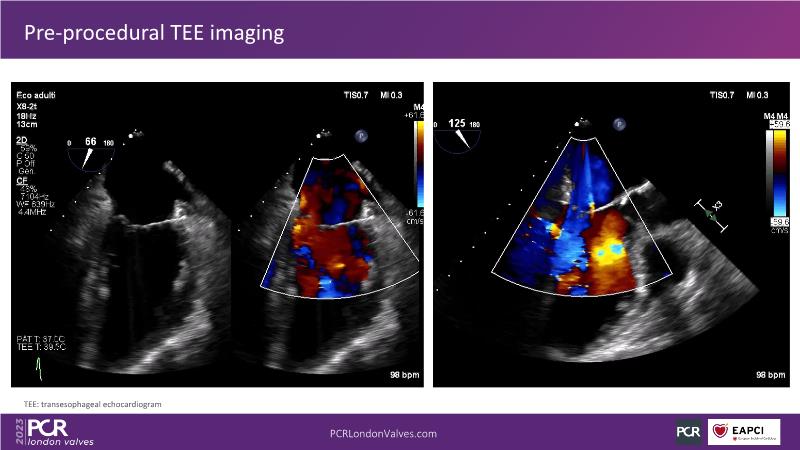

This session explores the features of the PASCAL Precision and the EVOQUE tricuspid replacement systems through simulators and case presentations, while a panel of experts discuss the technology, witnessing live demonstrations of treating mitral and tricuspid regurgitation patients.

- To learn about the differentiating features of the PASCAL Precision system showcased in a series of simulators alongside case presentations

- To interact with a panel of experts discussing the PASCAL Precision system technology and showcasing, live, its different key features in action and how they help treat mitral regurgitation and tricuspid regurgitation patients